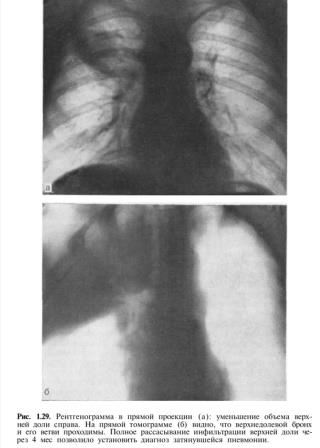

Особое значение имеет динамика процесса. При острой и затянувшейся пневмонии наблюдается благоприятное течение процесса, приводящее к рассасыванию, а при хронической пневмонии под влиянием лечения в лучшем случае наступают стабилизация и лишь небольшое рассасывание воспалительных изменений. Правда, эти факторы имеют лишь относительное значение. Нам приходилось наблюдать больных, которые поступали в клинику с диагнозом хронической пневмонии после лечения в стационаре, проводившегося 4 мес и более. В течение нескольких недель у некоторых из них под влиянием больших доз антибиотиков, проведения нескольких лечебных бронхоскопий, введения лекарственных веществ через зонд непосредственно в очаг поражения, рационального применения физических методов лечения удавалось добиться полного или почти полного рассасывания процесса. Динамика свидетельствовала о том, что на самом деле имела место не хроническая, а затянувшаяся пневмония (рис. 1.29).

.jpeg)